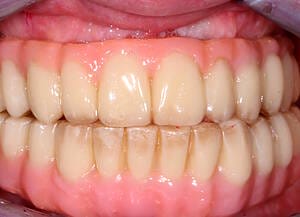

Natalie arrived at Wimpole Street Dental Clinic facing an extremely challenging dental situation. She had several missing and damaged teeth, infections in the bone, and significant bite issues caused by a long-term tongue habit. On top of that, she was a smoker and had developed a strong dental phobia over the years, making it difficult for her to seek help sooner.

The moment Natalie saw her new smile, the emotion was undeniable. What had once been a source of discomfort, anxiety, and embarrassment had been completely transformed. Her new teeth restored full function and aesthetics, giving her back the ability to eat, speak, and smile without hesitation.

This result was more than cosmetic. It marked the end of a long journey filled with fear and hesitation, and the beginning of a new chapter defined by confidence and well-being. Natalie’s story is a powerful example of how modern dentistry, when led by skilled professionals and supported by cutting-edge technology, can restore much more than teeth.

My first look in the mirror with my new set of teeth was incredible. I’m in disbelief and I feel a bit overwhelmed because it looks so good. At the same time, it looks so natural, it is the shape of my natural teeth and smile. They feel comfortable, I can speak with them. I feel very confident that this will work very well for me.